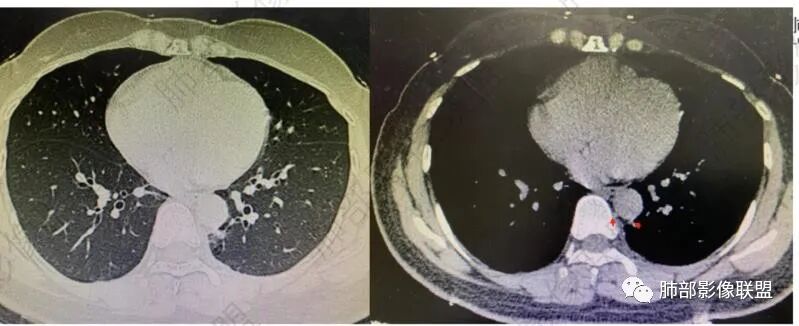

右肺上叶纯磨玻璃结节,界清,考虑aah或AIS。左肺下叶结块,界清不规整,内见空洞与支气管通,支气管壁增厚不明显,考虑肺隔离症,结核,腺癌不除外,建议CTA检查,视频两下肺多发磨玻璃结节,考虑炎性改变。

磨玻璃结节,建议抗炎治疗后复查。左肺下叶病灶建议CTA除外肺隔离症。

右肺上叶纯磨玻璃结节,界清,考虑癌前病变aah或AIS。左肺下叶结块,界清不规整,内见支气管扩张,支气管壁增厚不明显,考虑粘液腺癌,鉴别隔离症。隐球菌不大像。

隔离症——需要增强确定,看起来附近似有体动脉正常,没增强底气不足。

真菌?不太符合,因为囊腔。如果不考虑隔离症?就要警惕腺癌系列,总体看来不是很支持。

1、右肺上叶混合密度磨玻璃结节特征性较强,尤其是后段病灶,边界清楚,应高度警惕微浸润腺癌,这个不用纠结,我们可以等,定期复查行之有效。

左肺下叶背段脊柱旁病灶相当不规则,形态既不符合空洞,也未能围成一完整的囊圈影,未见典型的分叶、毛刺及清楚的磨玻璃晕,前方出入支气管轻度扩张,纵隔窗病灶密度偏高不均,临近胸壁未见侵入。双肺门及纵隔未见增大淋巴结。

客观评价,该病灶缺乏恶性肿瘤影像学特征,尽管我们不能排除恶性。

有时在临床上诊断慢性炎症其实比诊断肿瘤、结核、真菌更难,因为病原学找到了结核菌,结合临床、检验、影像等相关资料就可以确诊结核病,活检时发现有肿瘤细胞就可以诊断恶性疾病,病原菌找到真菌或者是血清学均确诊真菌感染。未能查实仍不能轻易排除,临床还需要治疗,观察,甚至手术切除送大病理。

2、临床实践中,左下叶背段类似阴影并不少见,支气管肺组织猬集纵隔旁,常为含气不良,或伴慢性炎症,长期存在。

结合本病例:年轻女性患者,体检发现病灶。影像学表现为左下肺类囊腔样结节,整体边界清楚,实性区域边缘平直、凹陷,缺乏典型分叶毛刺、胸膜改变等,病灶也未显示清楚的磨玻璃勾边,病灶不大而肺门纵隔未见肿大淋巴结,综合考虑慢性炎性肉芽肿可能性较大。必要时可结合病理检查。

肺隔离症也偏内侧,常表现为混杂密度,含液囊性病灶为主。须查实体循环供血证据。